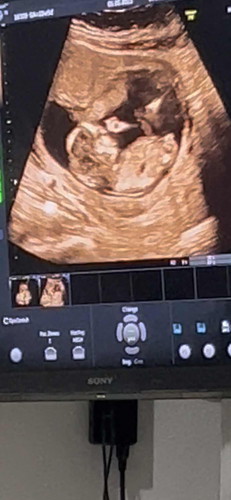

เมื่อวานไปฟังผลเลือดมา คุณหมอบอกว่าเราเสี่ยงสูง 1:169 ต้องส่งตัวเจาะน้ำคร่ำ พอได้ฟังรู้สึกใจสลาย เสียใจมากๆเลยค่ะ ร้องไห้จนไม่มีน้ำตาแล้ว มีแม่ๆคนไหนมีประสบการณ์แบบนี้มั้ยคะ โอกาศที่ผลเจาะน่ำคร่ำออกมาปกติ มีมั้ยคะ 😢😢😢 (เราอายุ24 แฟน31ค่ะ) #16w3d #ผลเลือดเสี่ยงสูง #ดาวน์ซินโดรม #ขอประสงการ์ณแม่ๆหน่อยคะ #ขอบคุณสำหรับคำตอบค่ะ